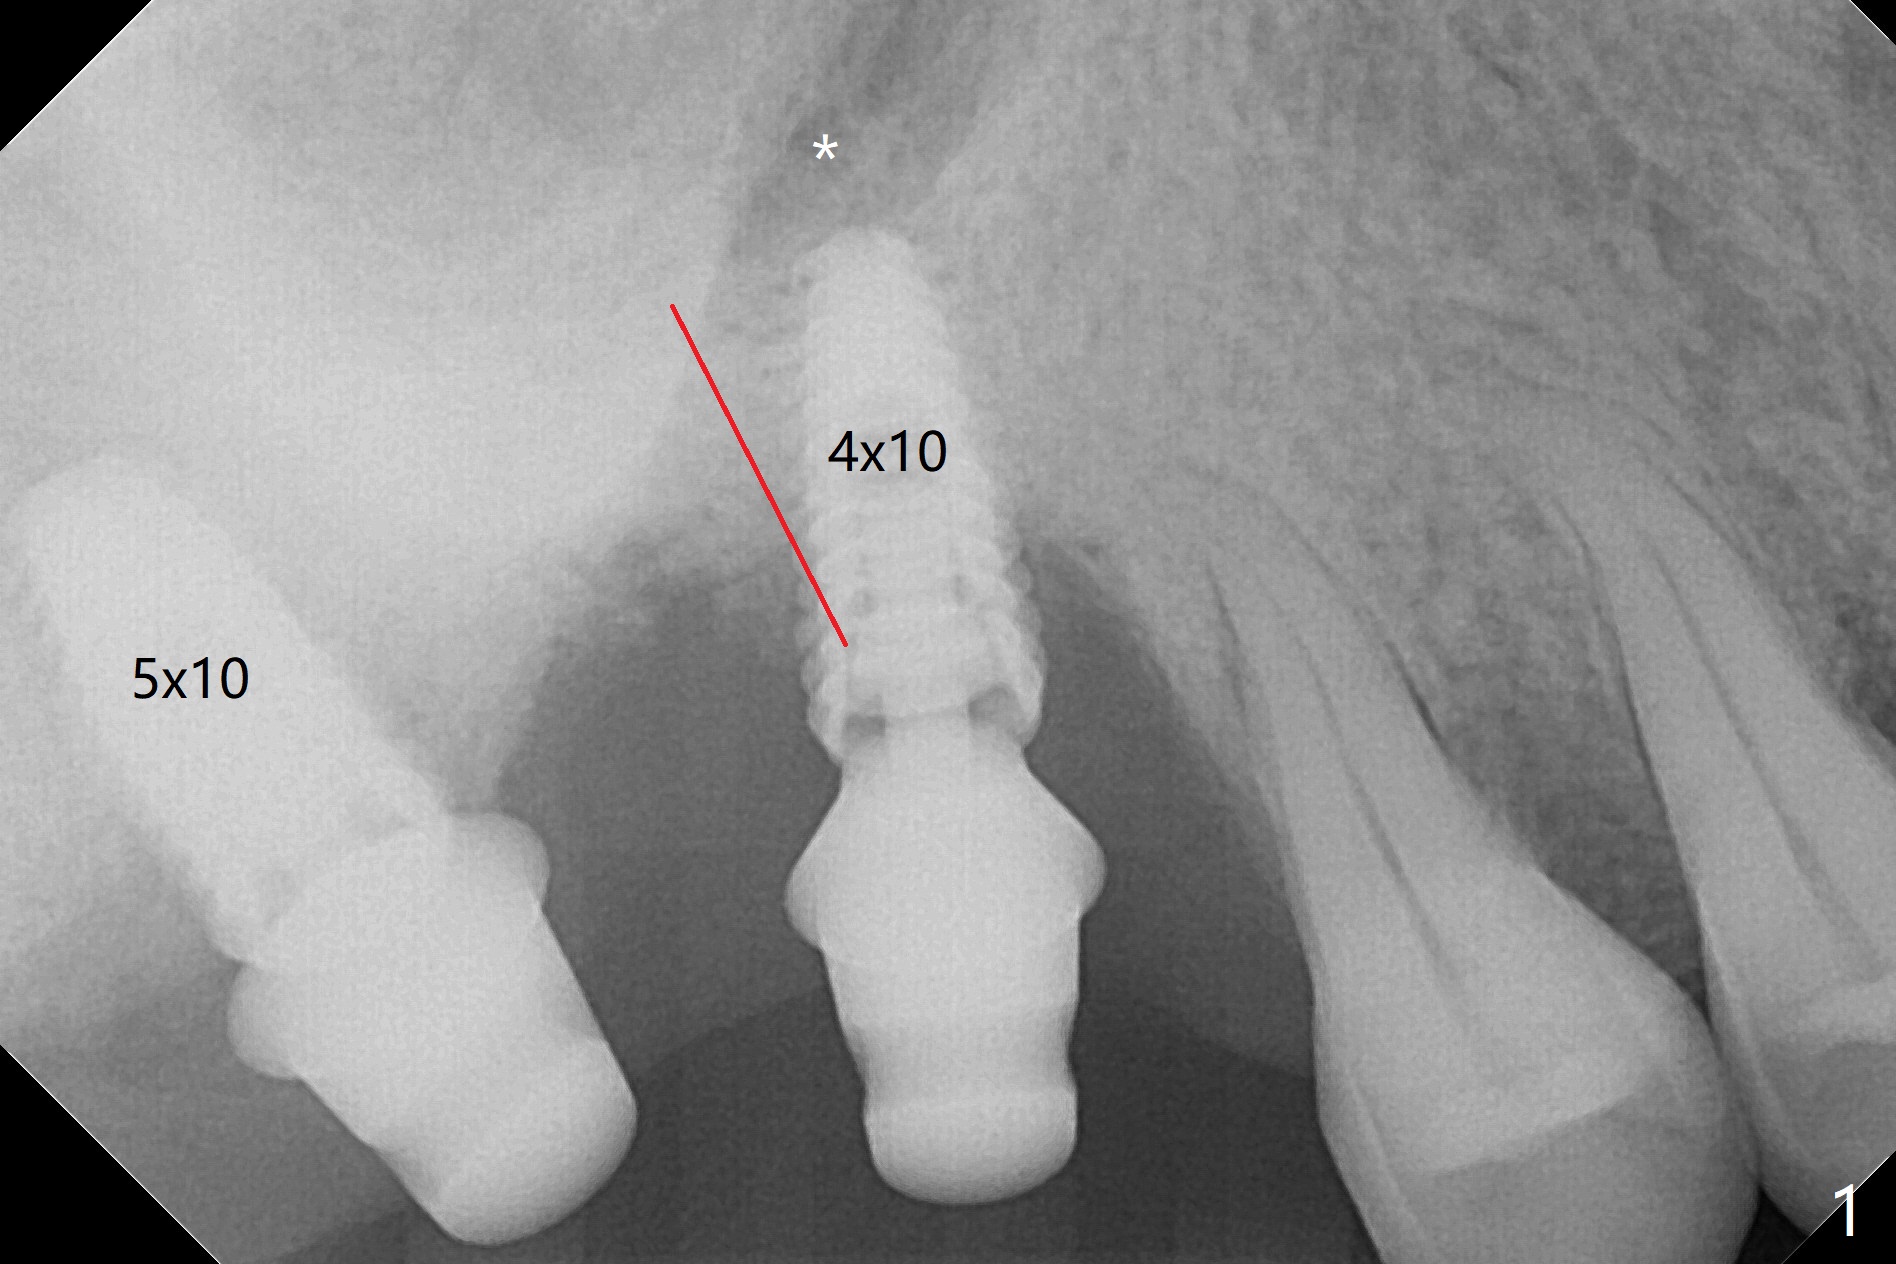

After use of 2.2 mm IS drill, DIO parallel pins are unstable at #2 and 3, partially due to shallow osteotomy. PA is not taken with parallel pins. When dummy implants are placed, the axis at #3 is noted; but instead of moving the apical end of the osteotomy distal (Fig.1 red line), the coronal end is moved mesial. By the time definitive implants and abutments are placed, the axis of #3 is parallel to that of #4, but close to each other (Fig.2,3). Orthogonal panoramic X-ray shows that they are critically close (Fig.4). If PA were taken with parallel pins after initial osteotomy, correction would be easy. The patient is doing fine postop without pain or nasal hemorrhage. There is no thread exposure 11 months postop (Fig.5). The abutment screw at #3 is retightened 7.5 months post cementation (Fig.6 (poor crown/implant ratio)).